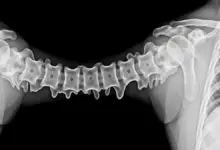

A coluna vertebral sustenta o corpo e serve de base para os movimentos do tronco. Ela é composta por vértebras que se conectam umas às outras, onde ligamentos mantêm essa união firme.

Entre uma vértebra e outra ficam os discos intervertebrais. Eles atuam como amortecedores, espalham a carga do dia a dia e ajudam a manter movimentos como flexionar, estender e girar com mais controle.

As curvaturas naturais, como a lordose lombar e a cifose torácica, fazem parte do desenho normal da coluna, ajudando a manter o tronco bem alinhado, amortecendo impactos e deixando a marcha mais estável e econômica.